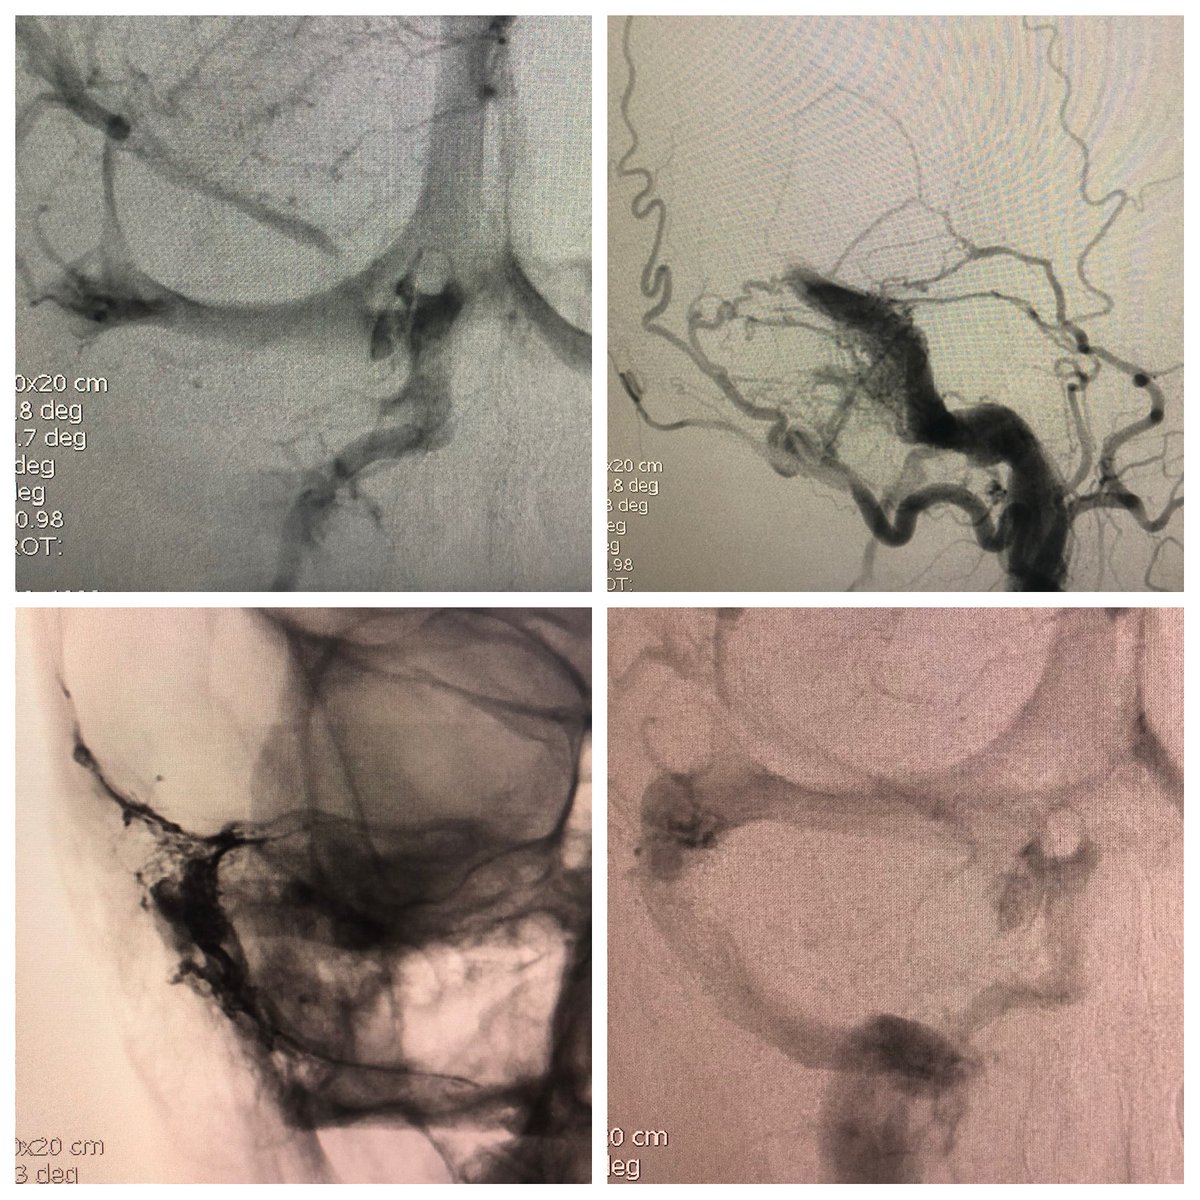

Good old double arterial catheter with simultaneous injection of Onyx 18 to cure a cerebelar ruptured AVM. Glad to have described with prof Mounayer this extraordinary technique.